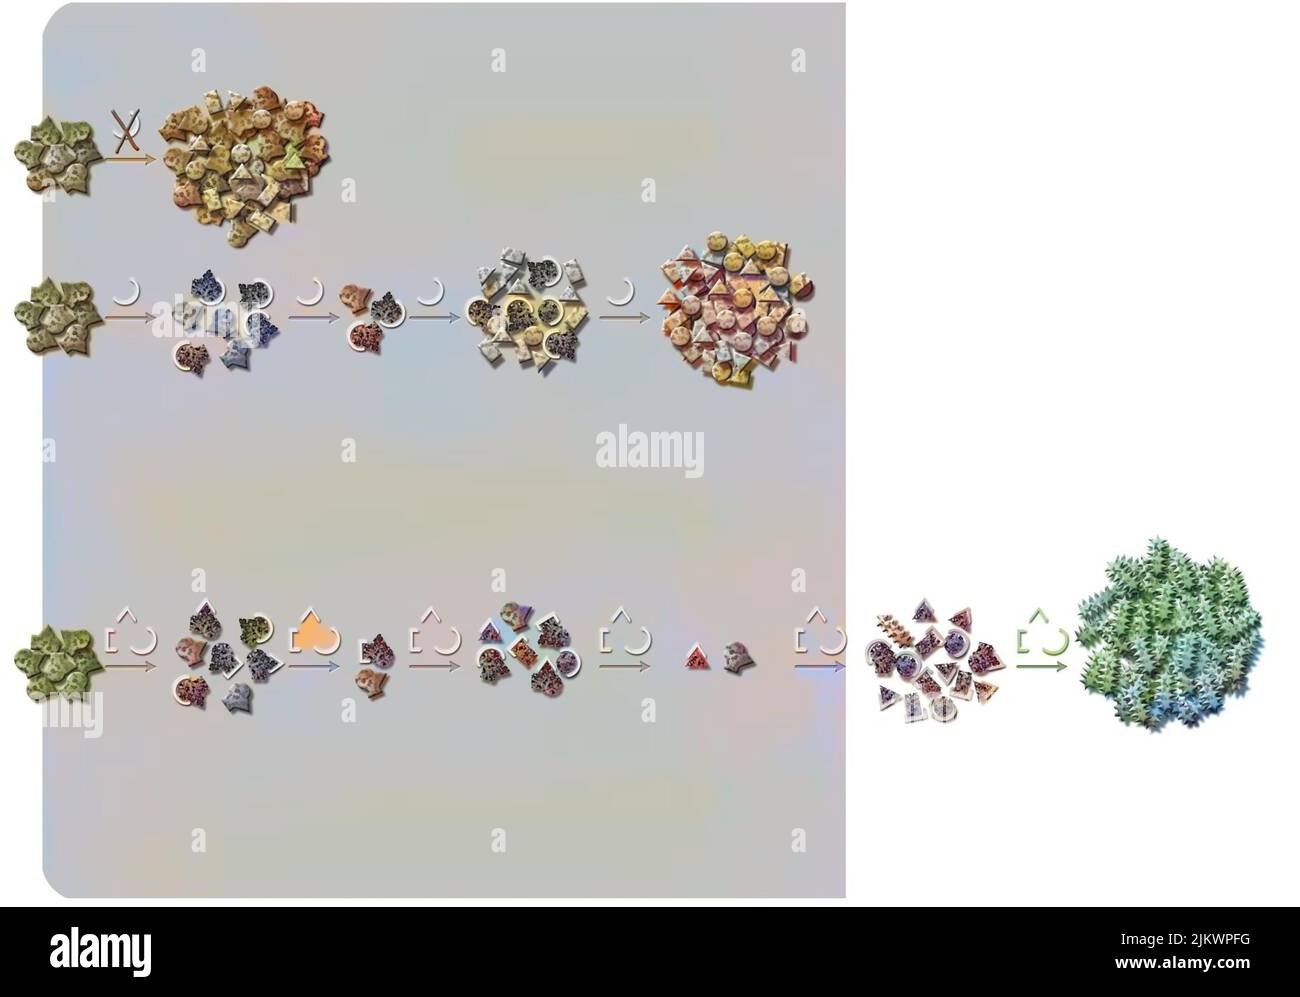

RF2JKWPG7–Troisième étape dans la façon dont le cerveau fonctionne quand vous tombez amoureux: La prise de décision.

RF2JKWPFG–Pourquoi utiliser la triple thérapie: Pour essayer d'arrêter le développement de la maladie du SIDA.